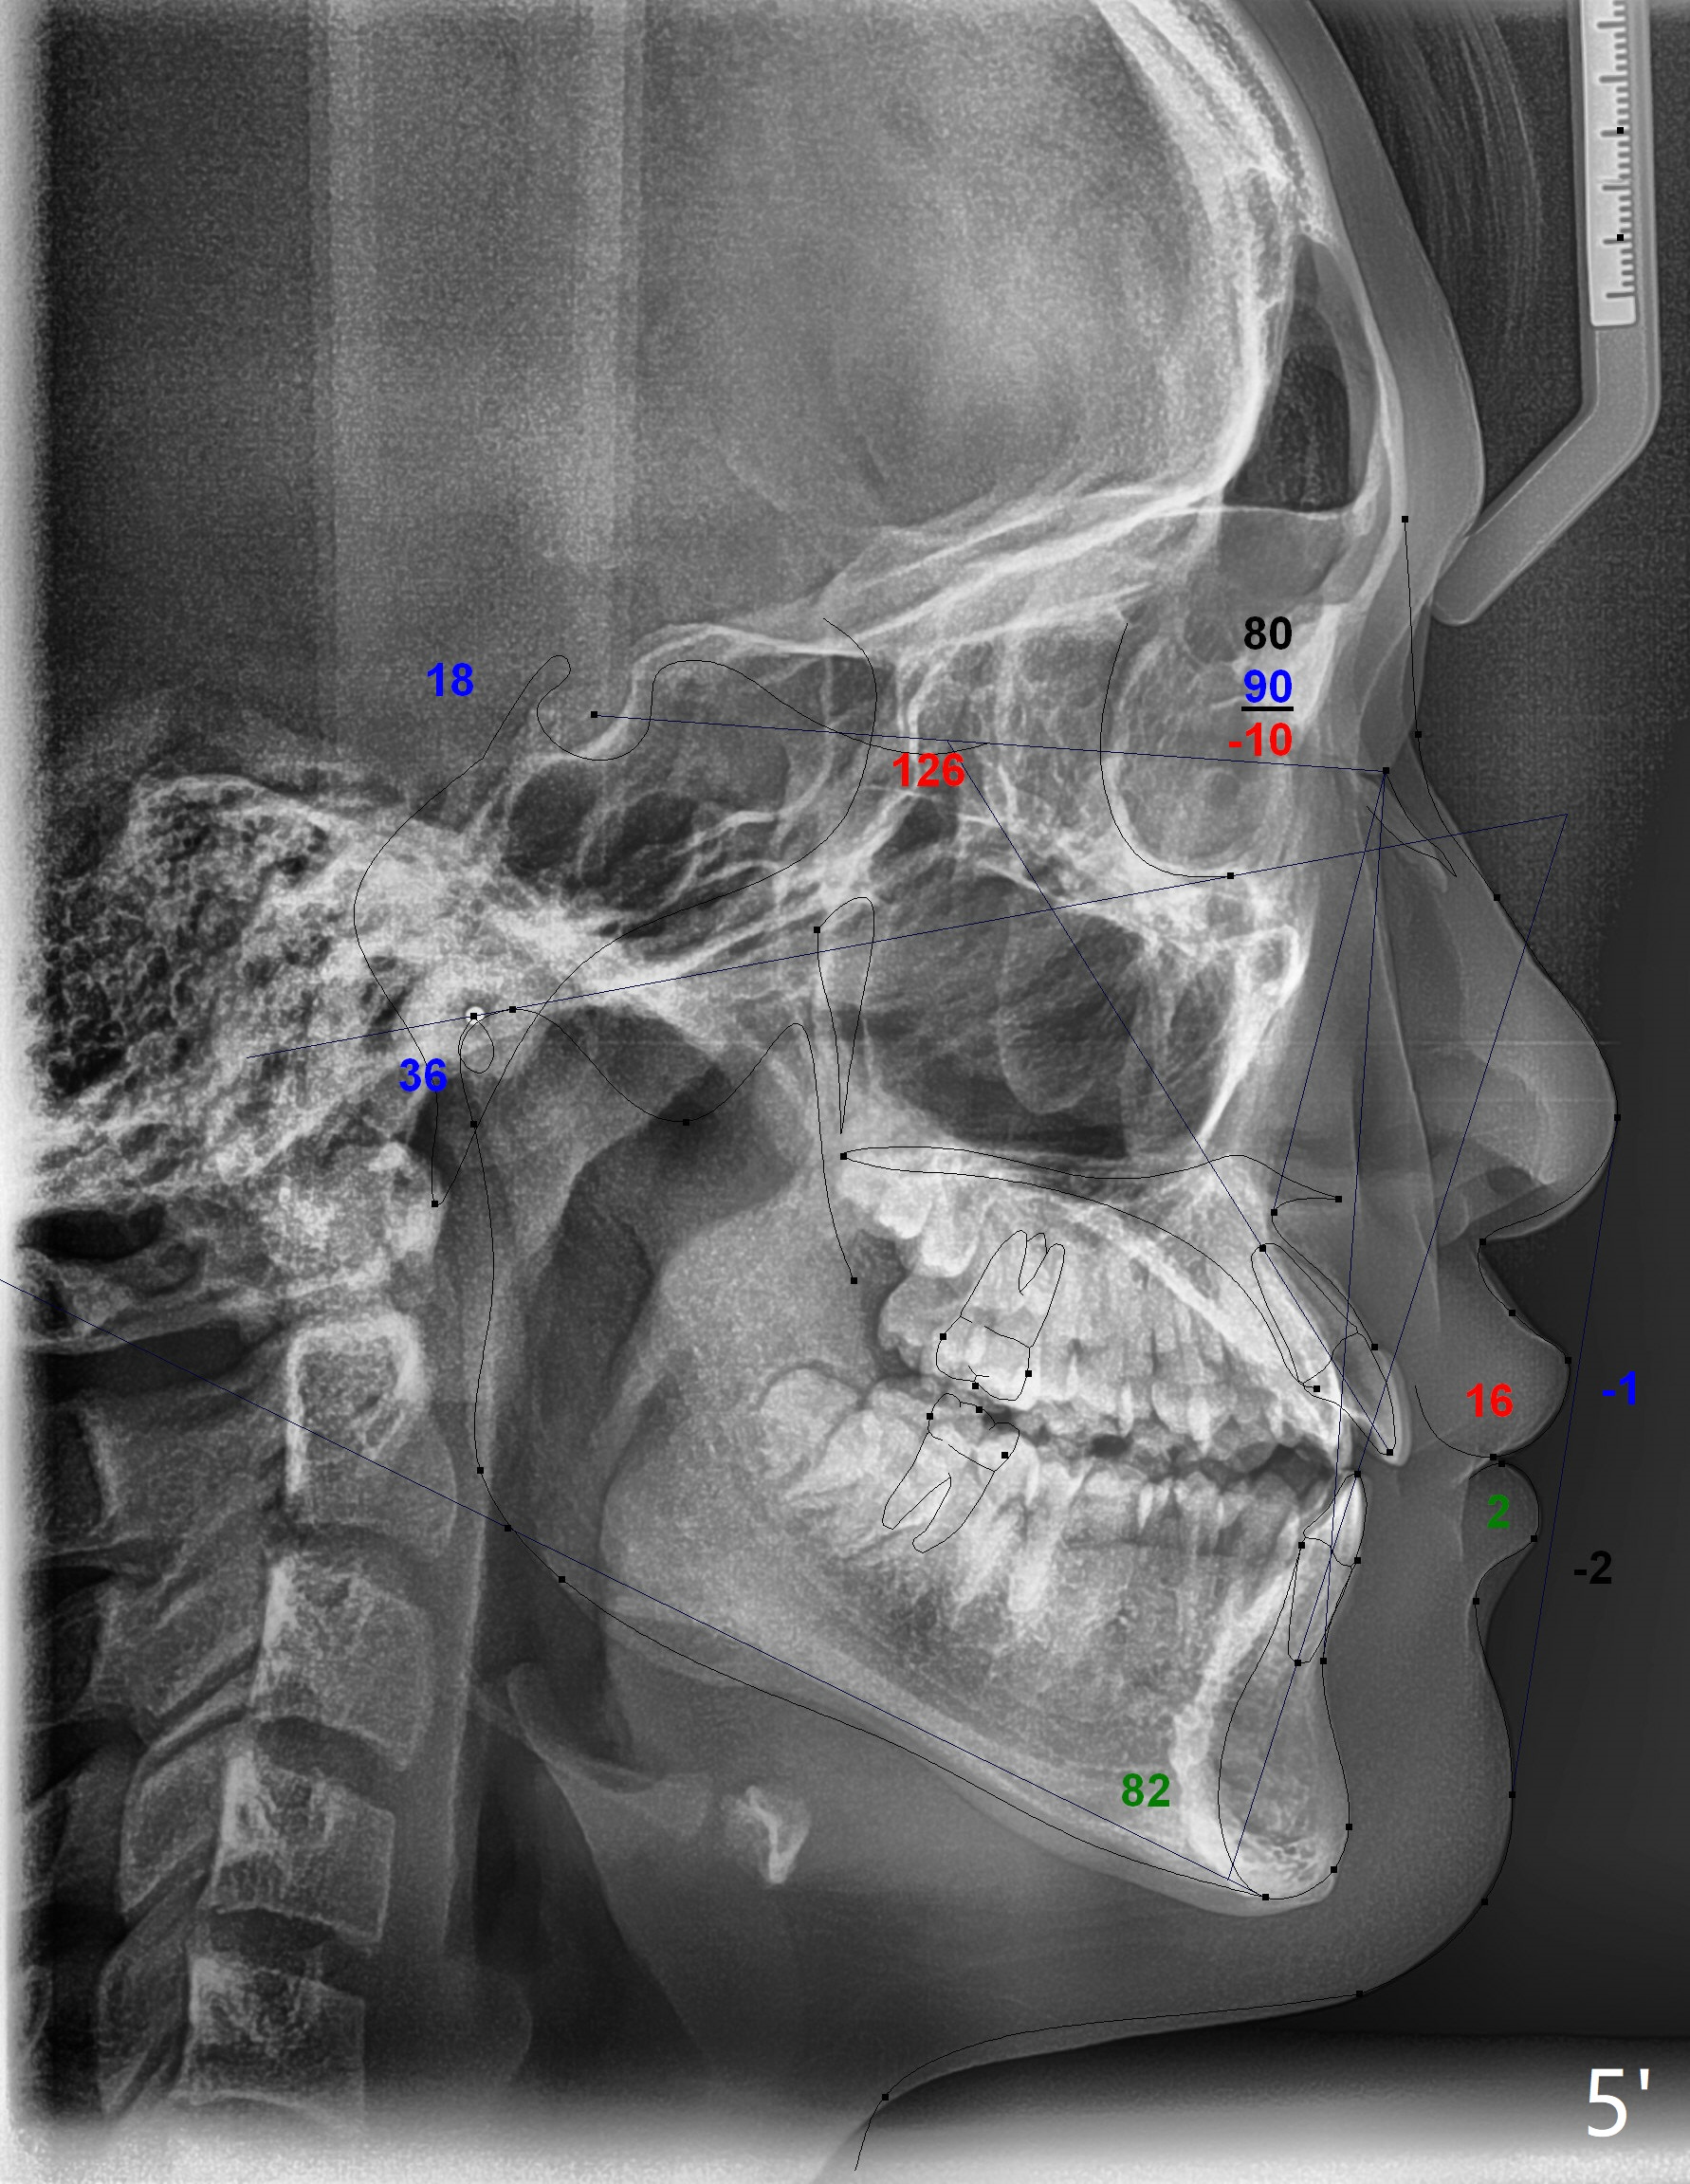

The upper dental midline of a 14-year-old man deviates the left (Fig.1,2,8) with midfacial concavity (Fig.3,4). The upper lateral incisors have cross bite, more severe on the left (Fig.6-8). Can we use open coil spring on the left first, a few months before the right, more or less to help correct the upper midline deviation? Cephalometric analysis shows Class III skeletal relationship (Fig.5,5',11).